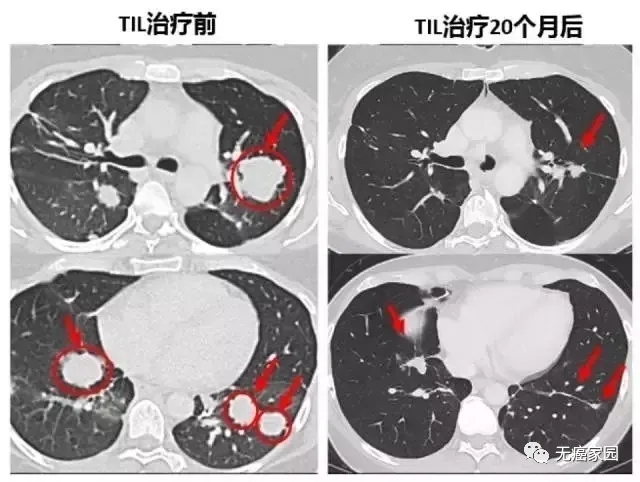

下面的对照图可以非常明显看到,第二次治疗前肺部布满的肿瘤,包括一些个头非常大的,第二次TIL治疗20个月后复查,这些肿瘤都非常显著的缩小了,专家认为这很可能是瘢痕。